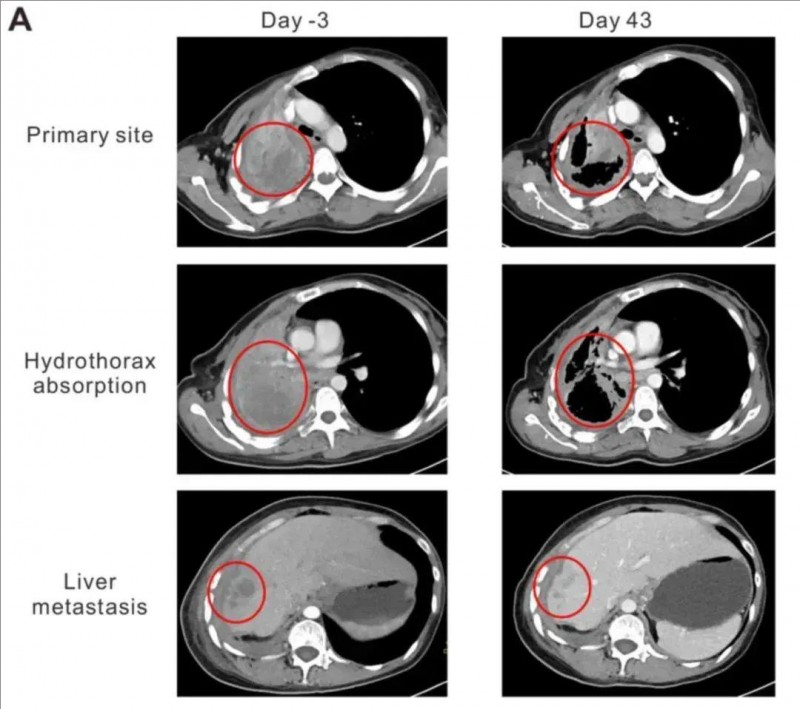

治疗效果堪称惊艳:TCR-T治疗后,依据RECIST1.1标准,该患者成功达到部分缓解(PR),卡氏功能状态评分(KPS)从50分大幅提升至90分,咯血与胸痛症状显著减轻。治疗第43天的CT影像显示,肺部原发灶从95×86×54mm缩小至64×44×54mm,肝部转移灶由19.8×19.6×20mm缩减至10×10×10mm;同时,胸腔积液完全吸收,肺组织重新复张。这些数据直观印证了NY-ESO-1 TCR-T疗法强大的抗肿瘤活性,不仅显著改善患者临床症状,更展现出逆转晚期癌症病情的巨大潜力。

▲图源“OncologyLetters”,版权归原作者所有,如无意中侵犯了知识产权,请联系我们删除